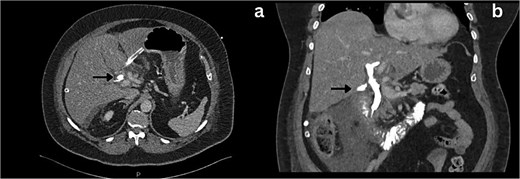

Following a brief clinical response to the initial conservative management for 24 hours, the patient started deteriorating and developed generalized peritonitis with worsening of inflammatory markers (C-reactive protein escalated to 438 mg/l). Consequently, she underwent an emergency diagnostic laparoscopy as the cause of peritonitis was not clear. Intraoperatively, it was observed that there was free bile in the peritoneal cavity, more so around the liver and the right paracolic gutter. There was also a bile collection behind the right colon and hepatic flexure of the colon, raising the possibility of a retroperitoneal source. The hepatic flexure of the colon was mobilized to assess the source of the leak. No obvious ongoing leak was noticed. As a precautionary measure, an Upper GI endoscopy was conducted intra-operatively to rule out any gastroduodenal perforation, as no obvious source of bile leak was seen from the biliary tree. This revealed the presence of bile in the stomach and confirmed normal anatomy up to the third part of the duodenum. The remaining intra-abdominal organs appeared unremarkable. Thorough peritoneal lavage was given, and 22 Fr abdominal drains were placed in the subhepatic, para-hepatic space, and pelvis, respectively, as the source of leak was not found. The following day, an endoscopic retrograde cholangiopancreatography (ERCP) was performed, which identified a small leak around the area of the cystic duct stump (Fig. 3). In response, a 5 cm-sized 7 Fr double pigtail stent was inserted into the CBD. A post-ERCP CT scan was performed to evaluate the contrast leak. The CT imaging revealed an extraluminal contrast leak originating from a defect in the posterior CBD (Fig. 4). Notably, the cystic duct stump remained intact and anterior, establishing the diagnosis of Spontaneous biliary leak from the CBD.

Axial and coronal section CT imaging revealing contrast leak from the bile duct; a) Contrast leak from the posterior aspect of CBD (arrow). b) Contrast extravasation into the subhepatic drain (arrow).